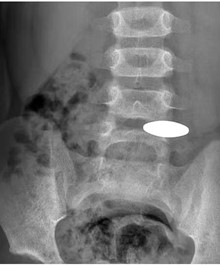

腹腔异物(硬币) 腹腔异物(铁丝)